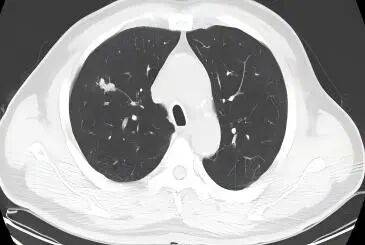

8周期后复查PET-CT提示:1.右肺小细胞肺癌复查,双肺见少许结节及斑点灶,代谢不高,请与旧片对比。2.颈部、纵隔、右锁骨上下区淋巴结,代谢不高。3.L3椎体代谢轻度增高,骨转移?

2025.8复查胸部+腹部CT、骨扫描、颅脑MRI,提示肿瘤无复发进展,肿瘤标志物正常,疗效评价维持PR。